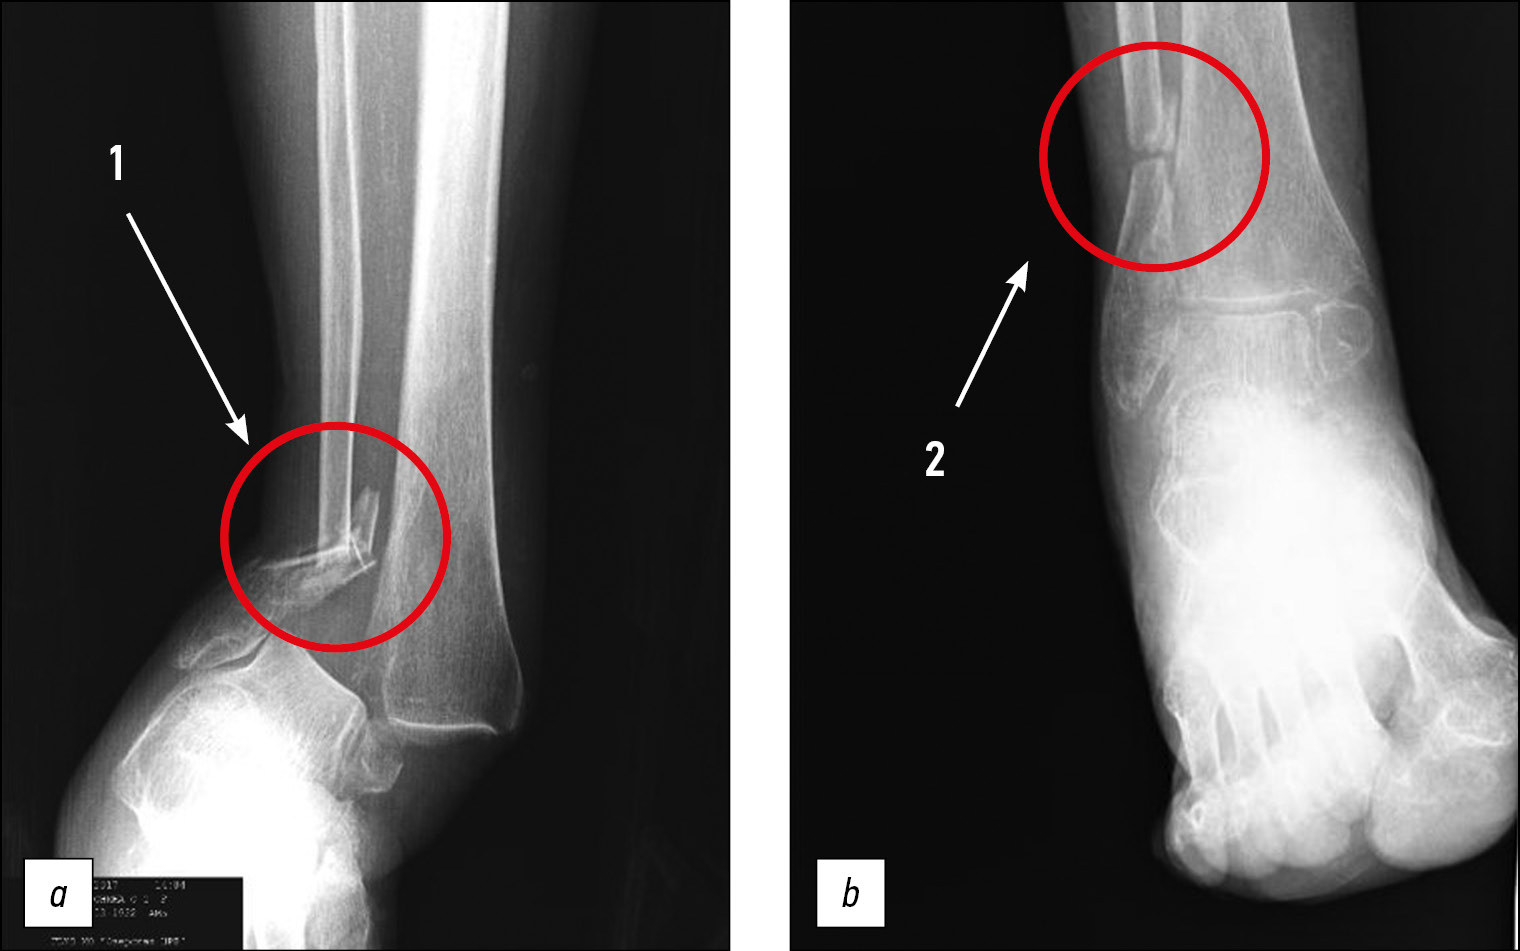

В рамках комиссионной экспертизы данные рентгенограммы изучены врачом-рентгенологом, которым констатировано следующее: «Определяются оскольчатый перелом нижней трети диафиза правой малоберцовой кости со смещением по длине и ширине, линейный перелом лодыжки правой большеберцовой кости со смещением, линейный перелом заднего края правой большеберцовой кости без смещения; соотношение костей в правом голеностопном суставе нарушено за счёт вывиха правой стопы кнаружи и кпереди. Края переломов заострены. Имеется расхождение костей правой голени в нижней трети за счёт разрыва дистального межберцового синдесмоза. Рентгенологических признаков консолидации не определяется» (рисунок).

Рис. Рентгеновский снимок правого голеностопного сустава в день травмы (а) и в динамике спустя 3 мес (b). Цифрами 1 (а) и 2 (b) обозначен оскольчатый перелом диафиза малоберцовой кости в нижней трети.

Fig. X-ray of the right ankle joint on the day of injury (a) and in dynamics after 3 months (b). The numbers 1 (a) and 2 (b) indicate a comminuted fracture of the fibular diaphysis in the lower third.